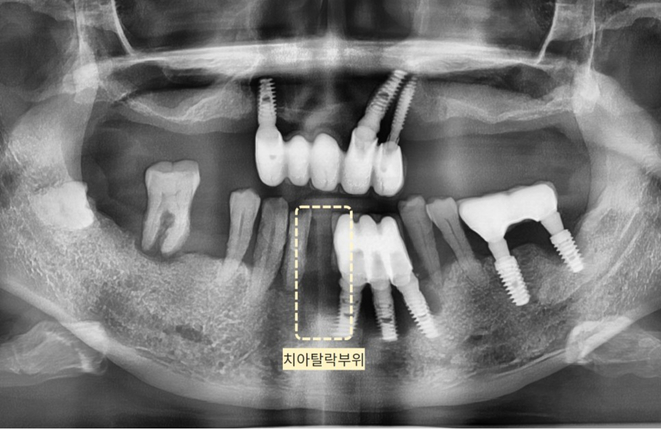

Như bạn có thể thấy trong bức ảnh bên dưới,

một số implant đã được trồng tại một nha khoa khác.

(Hình bên dưới) Tình trạng viêm xung quanh trụ implant đã cấy ghép trước đó khiến nướu bị tụt xuống và

chân răng (xương ổ răng) nâng đỡ răng bị mất khiến răng tự nhiên bị rụng.

(Ảnh bên dưới) Chúng ta hãy xem kỹ hơn bức ảnh toàn cảnh 3D.

Bạn có thể thấy đường viền nướu vốn đáng ra phải là

đường chấm màu xanh lam nay đã chìm xuống đường

viền màu vàng đậm nằm ở đầu chân răng.

Khi nướu đã tụt đến mức này thì việc răng rụng cũng không có gì lạ,

răng tự nhiên bên cạnh đã ăn sâu vào chân răng nên sẽ rụng sớm thôi.

(Hình bên dưới) Nếu quan sát tình trạng viêm xung quanh trụ implant,

bạn có thể thấy xương nướu ở vùng răng cấy ghép phía dưới đặc biệt bị lõm xuống so với các vùng khác.

(Vạch liền màu vàng là đường xương nướu)

Ngoài ra, xác nhận xương nướu răng hàm trên đã tụt xuống đáng kể, chỉ bằng một nửa so với trụ implant.

Cả hàm trên và dưới đều là những biểu hiện điển hình của viêm quanh implant.